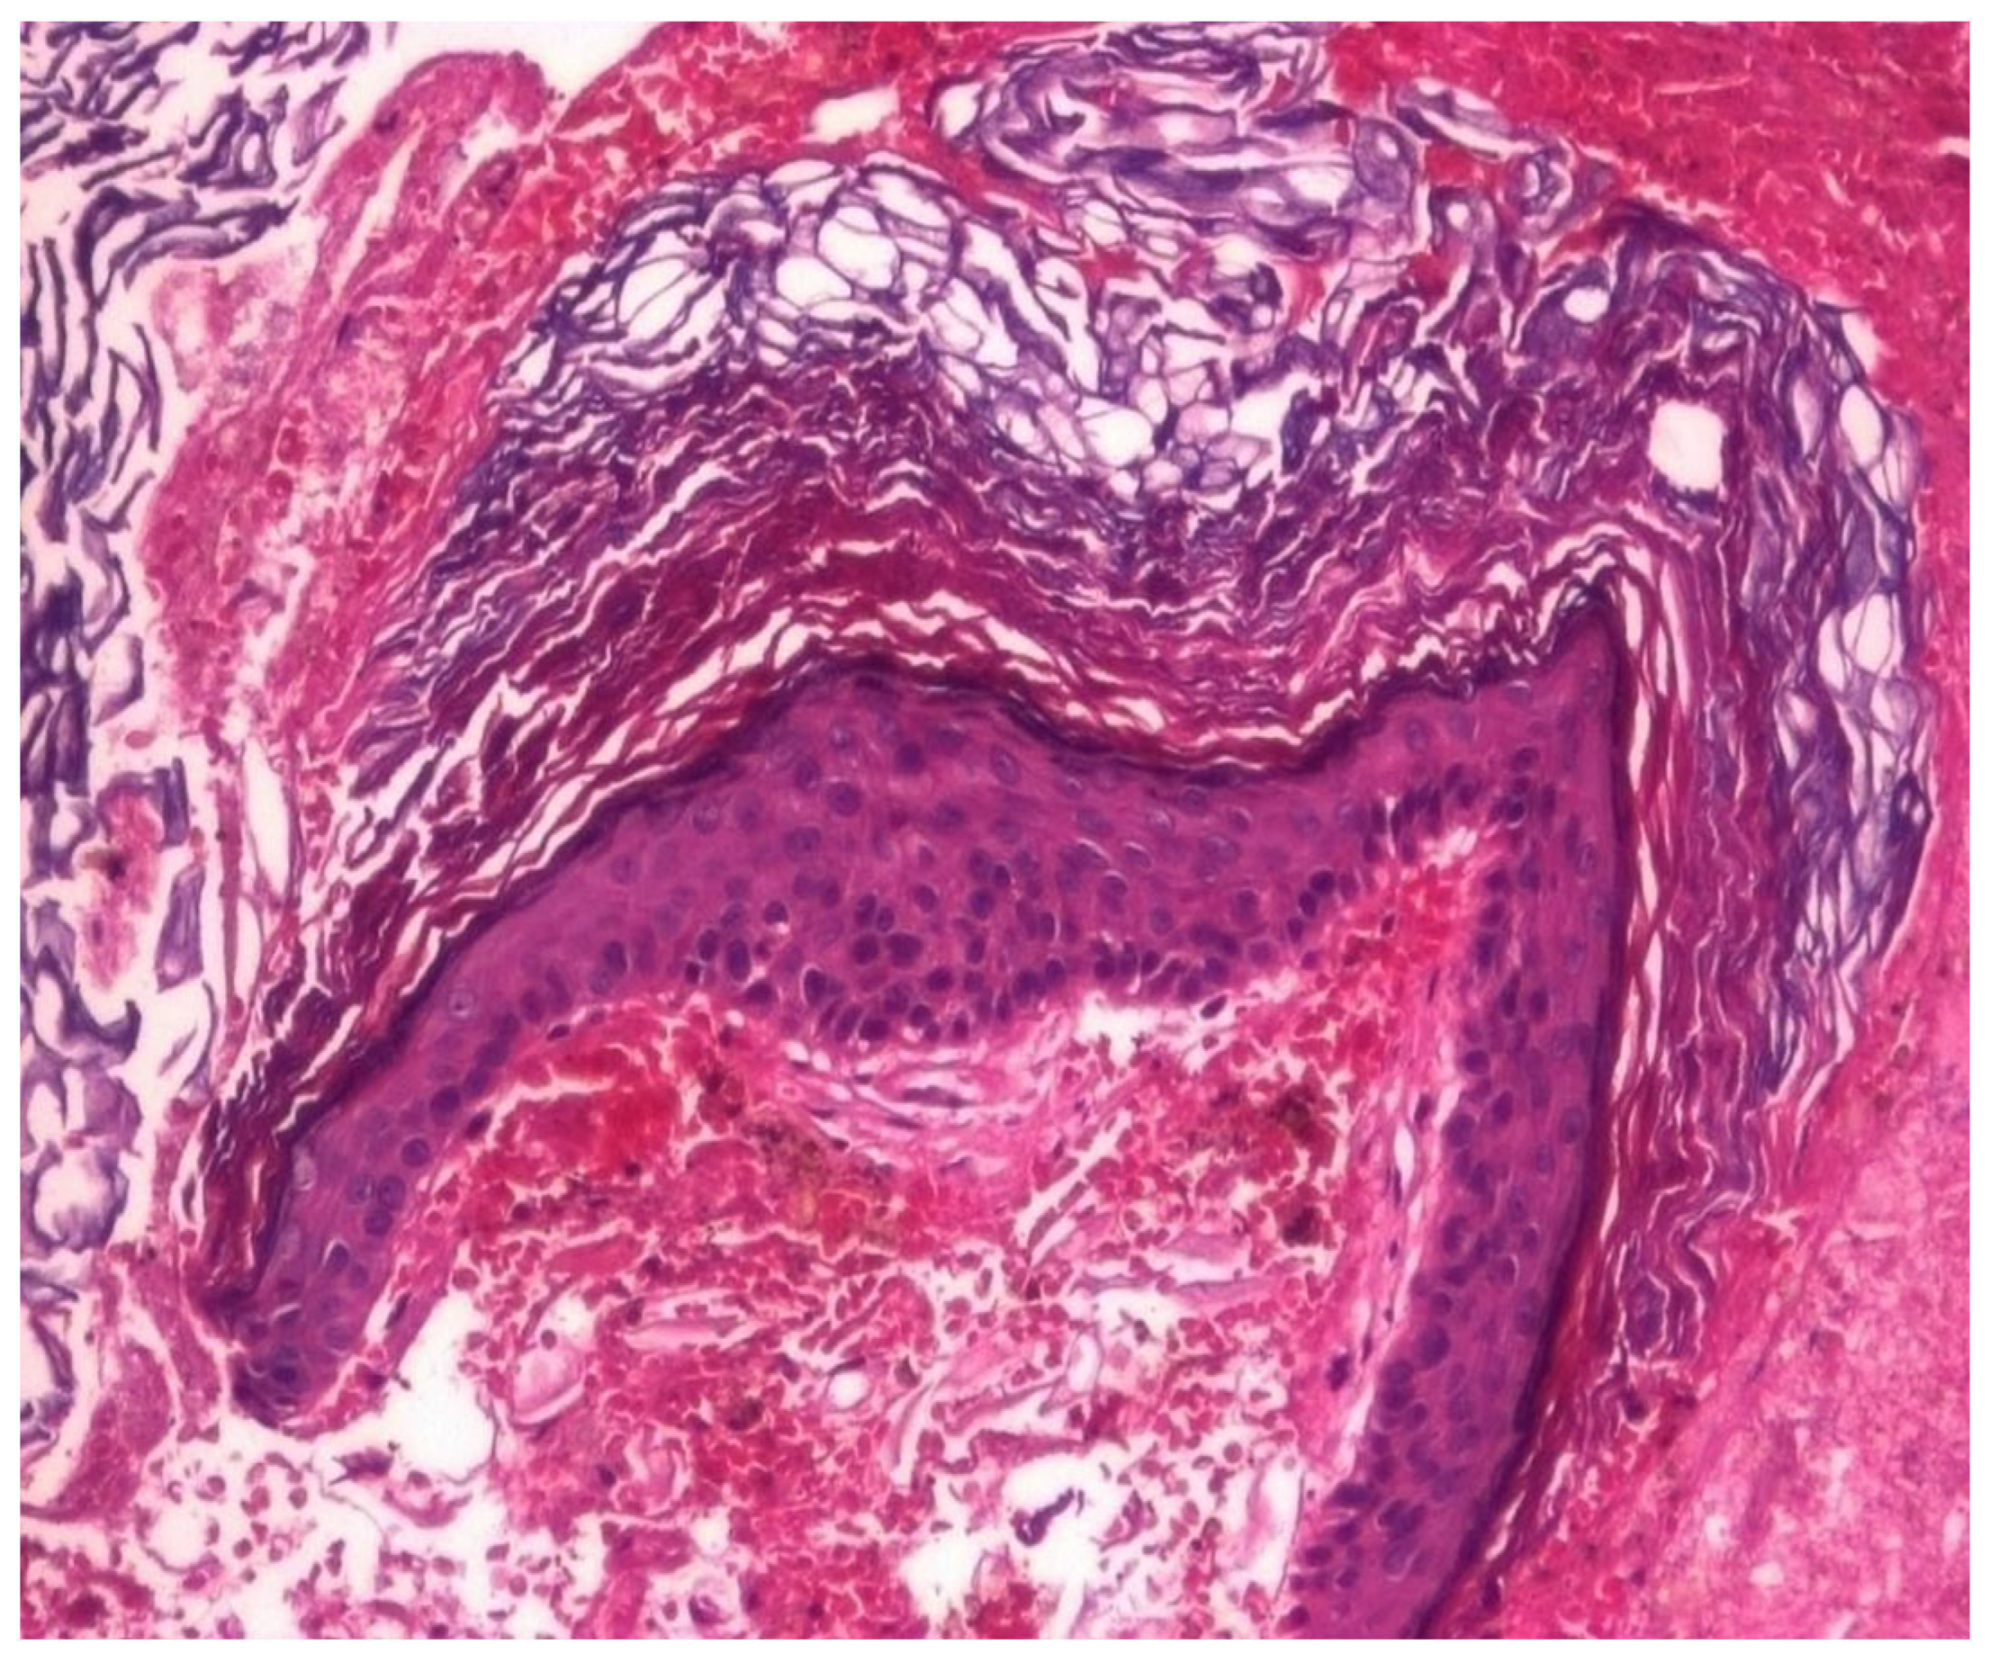

3.1.3. Analysis of Histopathologic and Immunohistochemical Results

| Histopathologic Aspects | Number of Patients |

|---|---|

| Cholesteatom | 276 |

| Polip | 180 |

| Tympanic membrane mucosa chamber, epithelium with apocrine-like cells, and chronic inflammatory infiltrate | 128 |